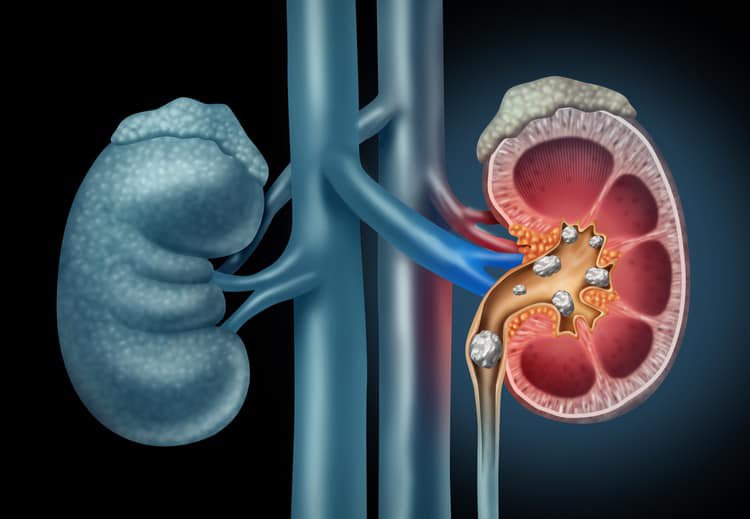

Sỏi thận là gì?

Sỏi thận là bệnh lý tại hệ tiết niệu thường gặp ở độ tuổi trung niên, từ 30 – 55 tuổi và tỷ lệ mắc bệnh nhiều hơn ở nam do nam giới có cấu tạo đường tiết niệu dài hơn và phức tạp hơn nên sỏi thường khó tự đào thải hơn ở nữ giới.

Sỏi tiết niệu là những phân tử rắn được hình thành do sự kết tinh tự nhiên của các tinh thể vô cơ có trong nước tiểu. Đa phần những viên sỏi bắt đầu hình thành từ thận, di chuyển dọc theo đường đi của hệ tiết niệu và bài tiết ra ngoài nên nhiều người quen gọi là sỏi thận.

Khi hệ tiết niệu bắt đầu hiện tượng lắng và kết tinh sỏi, những tinh thể và viên sỏi nhỏ thường đi theo đường tiểu và được bài tiết ra ngoài. Tại một vị trí nào đó trên đường niệu, tinh thể hoặc viên sỏi bị vướng lại, tiếp tục lắng và kết tinh tạo thành những viên sỏi kích thước lớn hơn.

Tại đây, sỏi kích thước lớn dần, có thể làm cản trở dòng lưu thông của nước tiểu dẫn tới ứ đọng nước tiểu, giãn phình ở phần trên vị trí tắc nghẽn. Chính tại vị trí này, sẽ xảy ra nhiều biến chứng như nhiễm trùng, kết tinh và hình thành thêm các loại sỏi khác nhau…, hậu quả cuối cùng là phá hủy từ từ cấu trúc thận, dẫn tới suy thận.

Dựa vào vị trí của viên sỏi trên đường tiết niệu mà sỏi có thể gọi tên hoặc phân loại khác nhau:

- Sỏi thận là sỏi nằm ở thận, gồm sỏi đài thận và sỏi bể thận.

- Sỏi niệu quản: do sỏi di chuyển từ bể thận xuống niệu quản và gây bế tắc đường tiết niệu.

- Sỏi bàng quang: 80% là do sỏi từ thận, niệu quản rớt xuống hoặc do bế tắc vùng cổ bàng quang, niệu đạo .

- Sỏi niệu đạo: khi sỏi theo dòng nước tiểu từ bàng quang xuống niệu đạo và bị mắc kẹt tại đây.